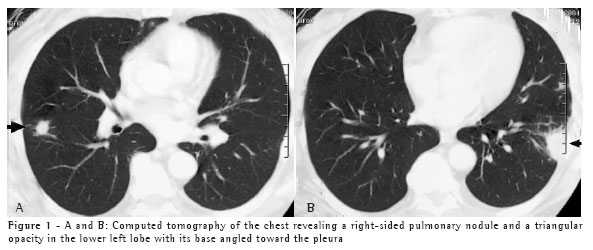

A 50-year-old white male, resident of the city of Blumenau and a stonemason, presented a clinical profile similar and simultaneous to that described in Case 1 ten days after the cleaning of the same area, in which there was bat guano. The patient was exposed to a large quantity of dust in an enclosed space. The patient was hospitalized for seven days. Two chest X-rays, one presenting diffusely disseminated micronodules in both lungs and one showing the subsequent control of the condition, are shown in Figures 2A and 2B.

Epidemiological history can raise diagnostic suspicion. Knowledge of clinical syndromes, together with clinical suspicion, can avoid the use of empirical treatment. Radiological findings, negative test results, and the high frequency of tuberculosis in Brazil were the motivations for prescribing tuberculosis treatment for both patients. Immunodiffusion test results, although negative for these two patients, have high sensitivity and are positive in approximately 75% of cases.(6) Length of exposure determines disease severity. This explains the fact that the second patient, who was the one who swept the area, presented a more severe form of the disease, with diffuse pulmonary alterations on the chest X-ray, and required hospitalization. However, a short exposure time results in focal pulmonary lesions, as in Case 1.